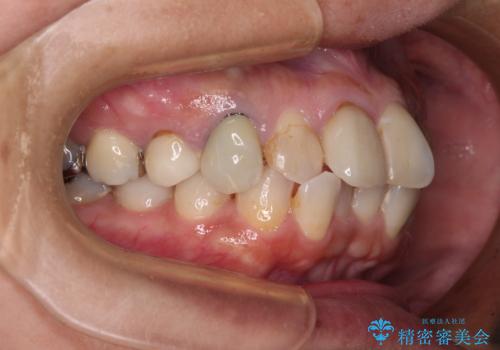

【モニター】処置歯の多い歯列 インビザラインでデコボコを整える

- 上下前歯のデコボコを気にして来院された患者様です。

歯列としては、ワイヤー装置でもインビザラインでも、どちらでも対応可能でしたが、処置されている歯が多く、ワイヤー装置を装着するためには処置歯のやり直しが必要な状態でした。

インビザラインでもアタッチメントを装着できないという同様のデメリットがありますが、比較的矯正治療を行いやすい歯列であったので、インビザラインによる矯正治療を行うこととしました。